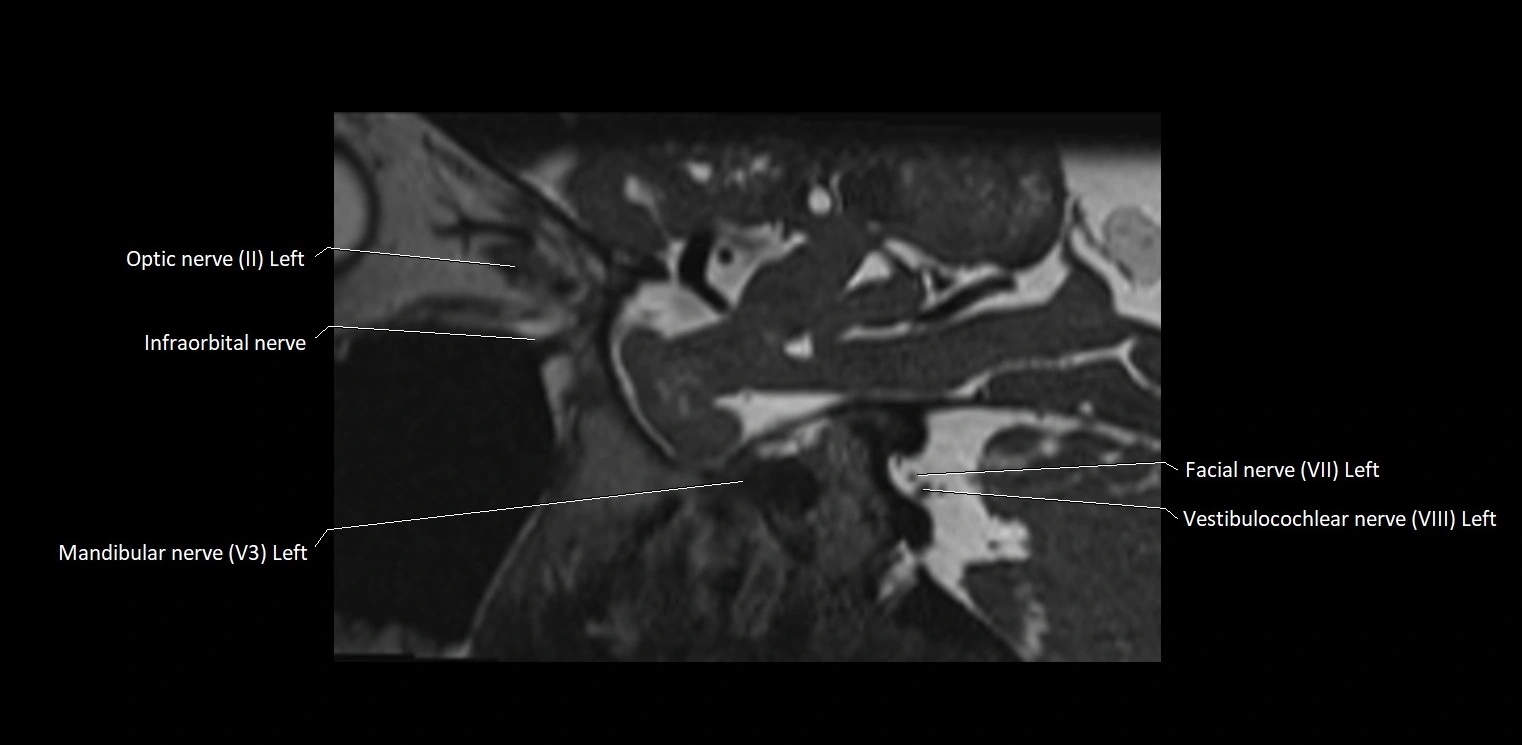

MRI Appearance

• The abducens nerve is a small, thin, linear structure

• Best visualized on high-resolution T2-weighted 3D MRI sequences (e.g., FIESTA or CISS)

• Seen as a hypointense (dark) line running from the brainstem at the pontomedullary junction, traversing the prepontine cistern, and entering Dorello’s canal under the petrosphenoidal ligament, then into the cavernous sinus, and finally the orbit

• May be challenging to visualize in standard MRI due to its small size

• Pathology may be inferred by absence, displacement, or enhancement of the nerve

MRI images

image